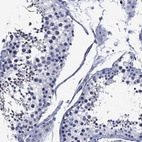

Immunohistochemical staining of human testis shows moderate cytoplasmic positivity in cells in seminiferous ducts.